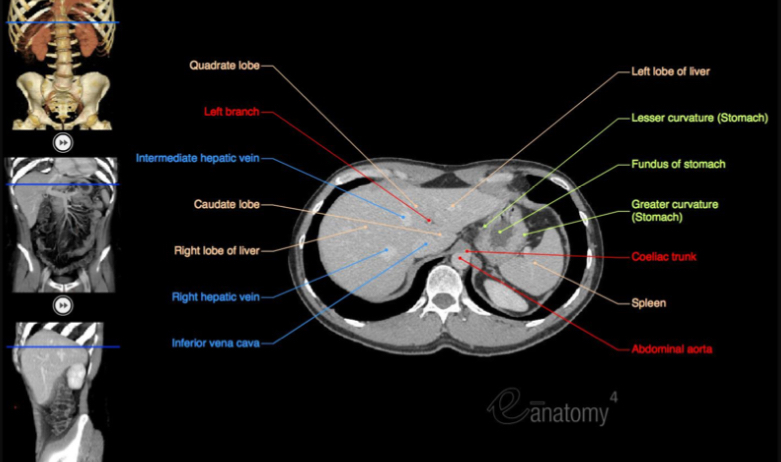

Label the viscera on the abdominal x-ray.

How can we get a high resolution picture of the abdomen, but why may this method not be chosen?

How can CTs replace a colonoscopy?